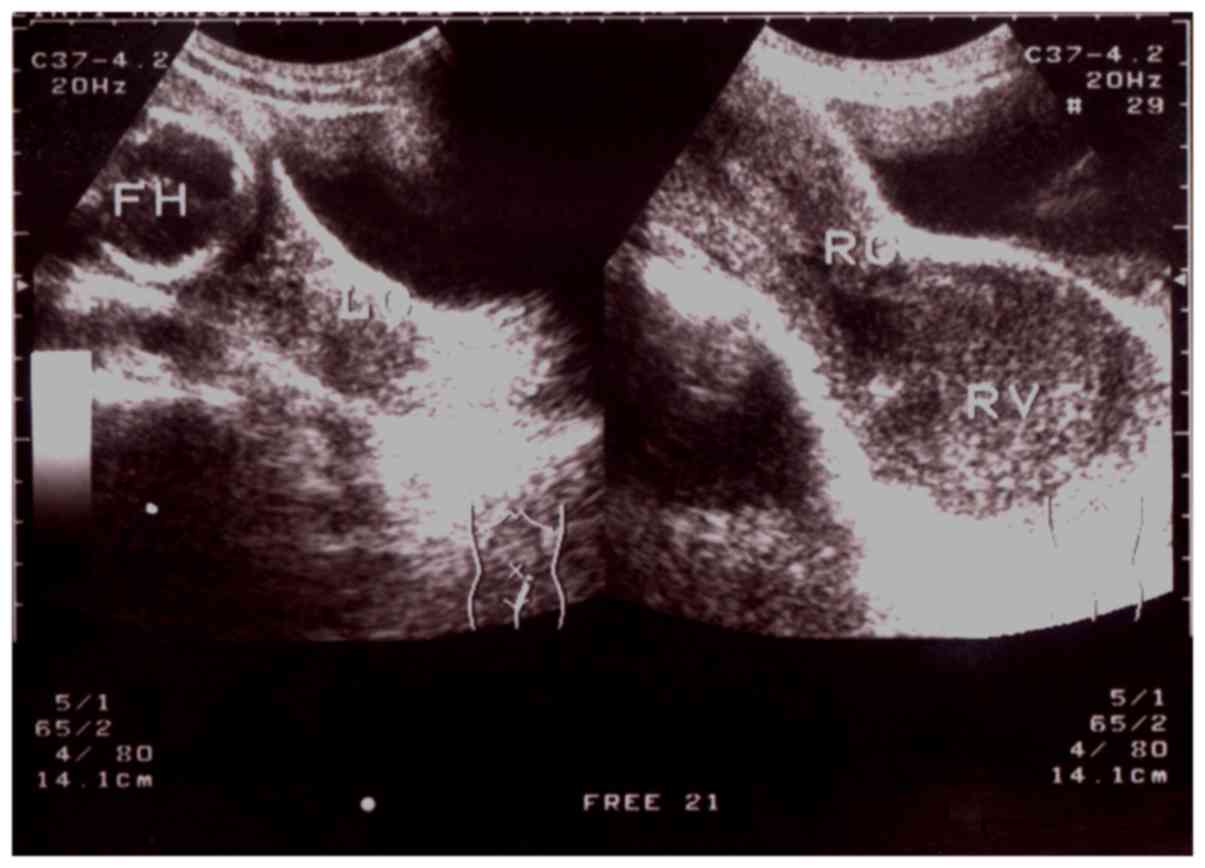

Out of the 15 patients with type I CVOS, there were 9 patients with right oblique septum and 6 patients with left oblique septum (Figs. 2–4). Among the 4 patients with type II CVOS, 3 patients had oblique septum on the right side and another on the left of the vagina (Fig. 5). In the 2 patients with type III CVOS, the septum was on the right side of the vagina (Fig. 6). Patients with types II (n=4) and III (n=2) CVOS exhibited an anechoic vaginal mass with an irregular shape and thickening wall, which was consistent with pathological findings.

Figure 6.

Type III congenital vaginal oblique septum syndrome. Sonograms obtained from a 17-week pregnant 32-year-old female patient with sagittal pelvic planes exhibiting the fetal head in the left uterus and the cystic mass with dense floating echogenic dots behind the right septum vaginal cavity. FH, fetal head; RV, dense floating echogenic dots behind the right septum vaginal cavity; RU, right uterus; RC, right cervix; LC, left cervix.

Out of the patients included in the current study, one patient aged 32 years old was diagnosed with type III CVOS whilst pregnant. CVOS diagnosis during pregnancy is rare and the patient's abdominal pain was reduced due to the absence of menstruation following pregnancy. However, due to persistent purulent secretion, part of the reclined septum was removed transvaginally when the patient was 17 weeks pregnant. At 40 weeks pregnancy, the fetus was in the breech position and the umbilical cord was around the neck of the fetus; therefore, a cesarean section was performed. During surgery, two cervical fistulas located below the gorge and a double uterus with fallopian tubes and ovaries on their side were identified.